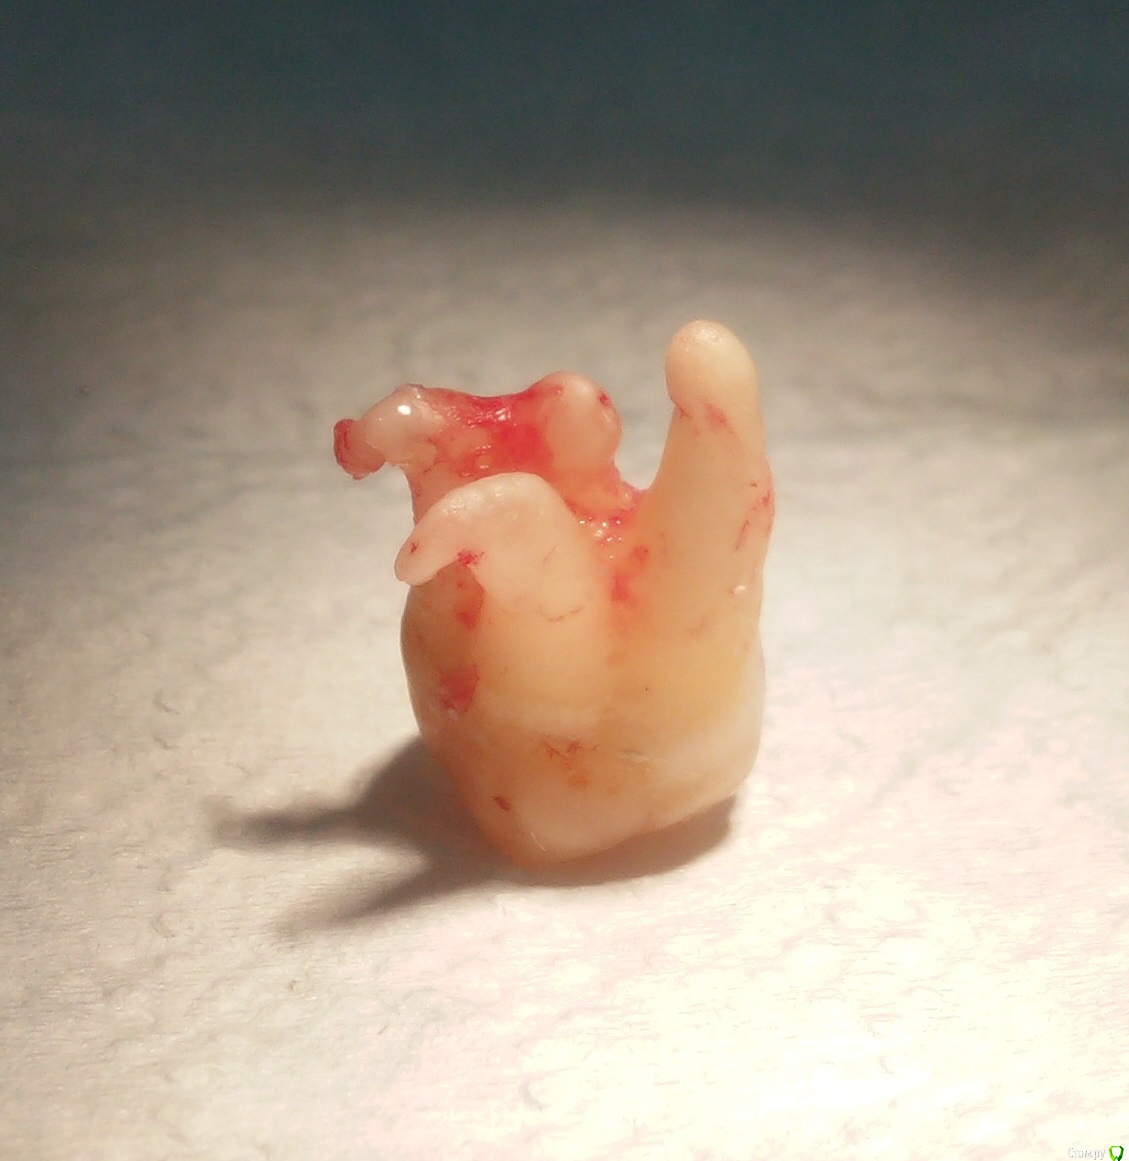

Фарид Расулыч Опубликовано 8 мая, 2015 Поделиться Опубликовано 8 мая, 2015 Засранец на выходе сделал "хрусть" ))http://s006.radikal.ru/i214/1505/bf/6b3a753040b4.jpg 6 Ссылка на комментарий

chervoncevdaniil Опубликовано 8 мая, 2015 Поделиться Опубликовано 8 мая, 2015 Засранец на выходе сделал "хрусть" ))http://s006.radikal.ru/i214/1505/bf/6b3a753040b4.jpgЧем доставали апекс? Ссылка на комментарий

Фарид Расулыч Опубликовано 8 мая, 2015 Поделиться Опубликовано 8 мая, 2015 (изменено) терапевтической гладилкой.На удаление основной части зуба ушло 5 минут. Корешок + 15 минут Изменено 8 мая, 2015 пользователем Фарид Расулыч Ссылка на комментарий

chervoncevdaniil Опубликовано 8 мая, 2015 Поделиться Опубликовано 8 мая, 2015 Прямым элеватором со стороны 7 вывихивали?Кость пилили где нибудь? Ссылка на комментарий

Фарид Расулыч Опубликовано 8 мая, 2015 Поделиться Опубликовано 8 мая, 2015 В основном прямым. Кость только чуть чуть. Чтоб гладилкой зацепиться Ссылка на комментарий